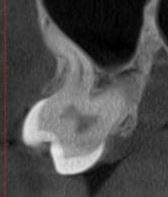

При плануванні імплантації лікарю важливо знати дві речі: об'єм кістки та точне розташування нервів.

КТ дозволяє провести віртуальну операцію: встановити імплант у програмі, виключивши будь-які ризики травмування пацієнта.